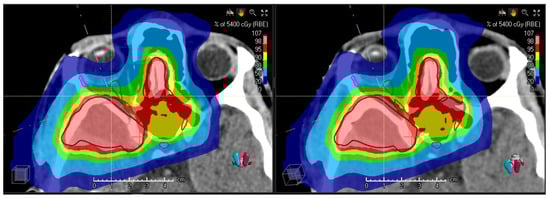

3.1. Validation of the Synthetic CTs—Results

3.2. Preliminary Results of the Clinical Study